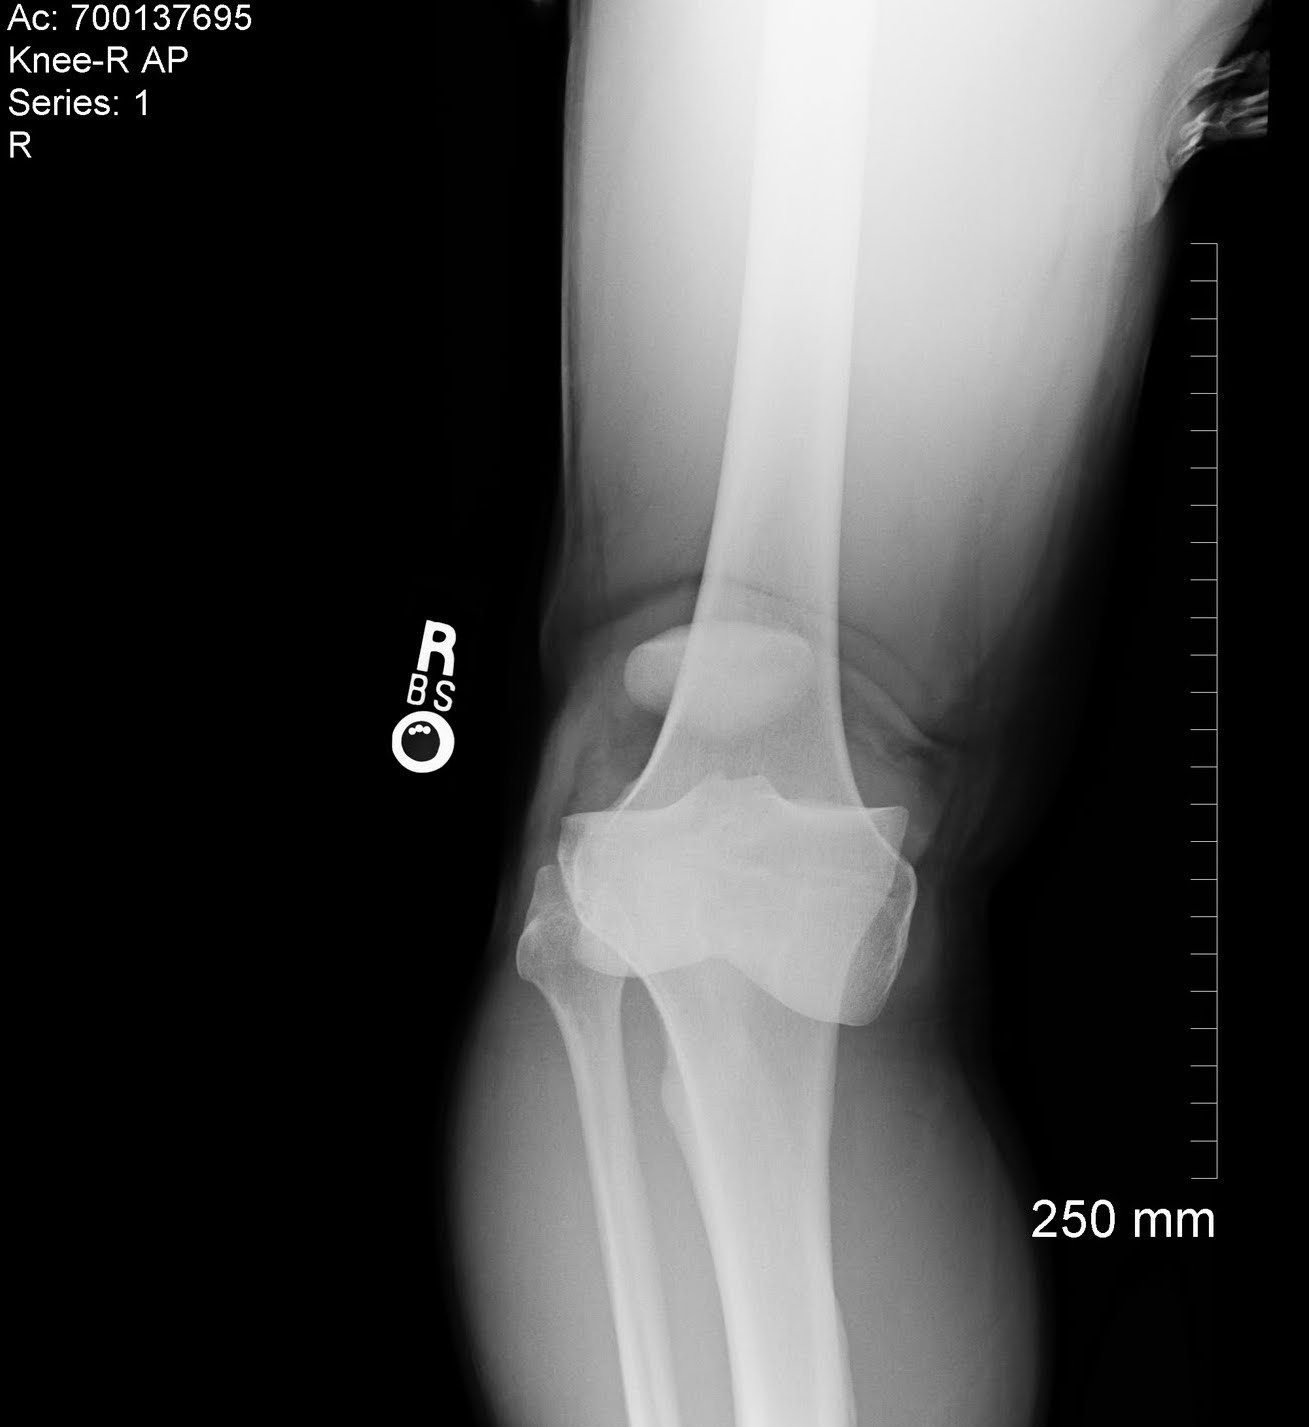

From radiopaedia.org

Lateral knee dislocation Image What Is A Dislocated Knee A dislocated kneecap is a common injury when a person changes direction suddenly with their feet planted on the ground — such as during sports or when dancing. A dislocated knee is when the three bones of your knee are out of place and aren’t aligned the way they should be. It is a severe injury that requires immediate medical. What Is A Dislocated Knee.